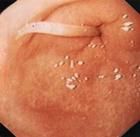

蛔厥是因腸寒胃熱,或肝膽氣機紊亂,或因驅蛔不當,以致蛔蟲竄入膽道而成。以突發上腹鑽頂樣絞痛,或伴嘔蛔等為主要表現的痛病類疾病。

本病即西醫學所說的膽道蛔蟲病。若治療不徹底,有可能並發膽癉、膽石等病。

4.白細胞總數稍高,嗜酸粒細胞增加。糞便、嘔吐物可查到蛔蟲卵。B超檢查或可發現膽道內有蛔蟲陰影。